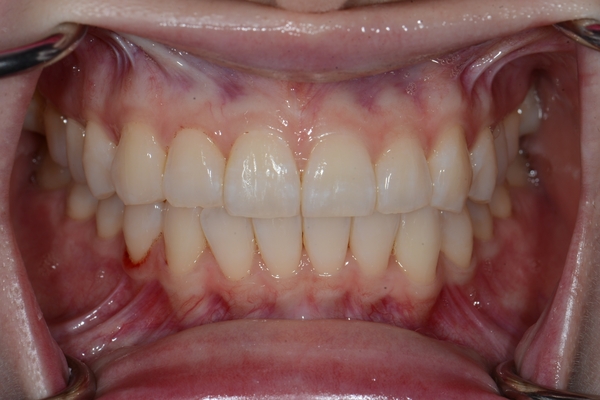

ガタガタとした歯並びや八重歯(叢生)CASE69